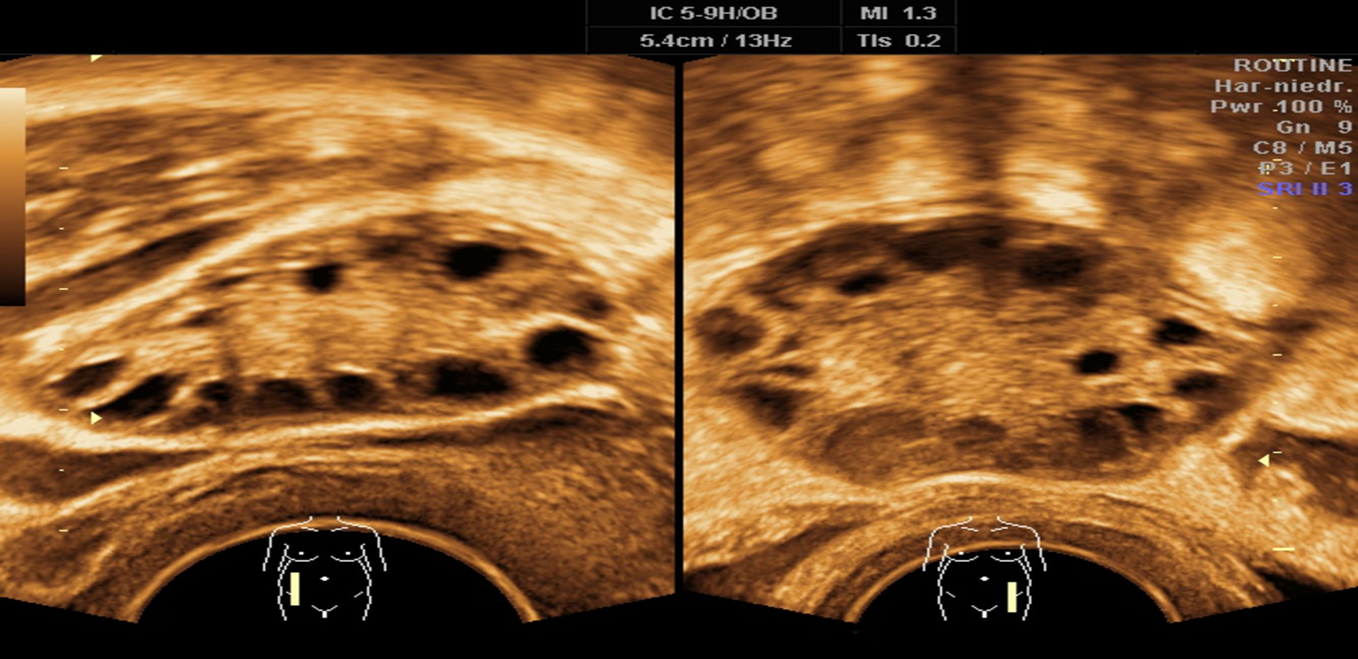

Transvaginal ultrasound of the right and left ovary:

both ovaries contain multiple anechoic, subcapsular cysts with a “string of pearls” appearance and posterior acoustic enhancement. There is a relative increase of stromal tissue and capsule thickness with increased ovarian size.

increased ovarian size (marked in green). This is a typical finding in polycystic ovary syndrome.